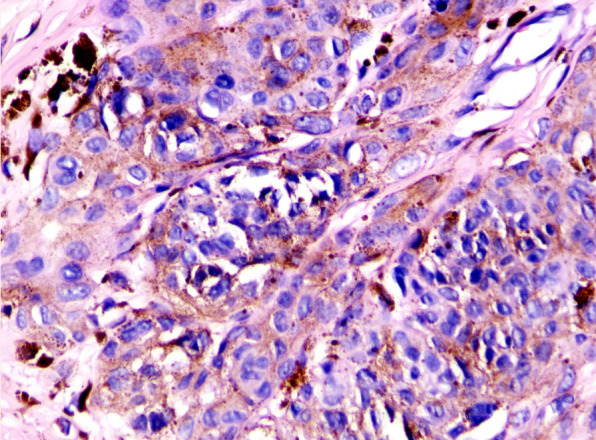

第5版世界卫生组织皮肤肿瘤分类(2022)对命名和诊断进行了修改。以下讨论了重要差异。每一类皮肤肿瘤的变化都有详细的描述,特别强调我们对皮肤不同肿瘤景观的分子发病机制的理解取得了有意义的进展。

The 5th edition WHO Classification of Skin Tumors (2022) has introduced changes to nomenclature and diagnostics. Important differences are discussed below. Changes in each category of skin tumor have been detailed, with particular emphasis on meaningful advances in our understanding of the molecular pathogenesis of the skin's diverse tumor landscape.